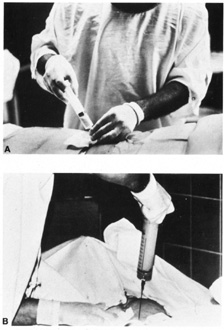

are a full cytogenic karyotype.  Fig. 3. A and B: Withdrawal of amniotic fluid with 20-gauge needle and 30-mL

syringe. Fig. 3. A and B: Withdrawal of amniotic fluid with 20-gauge needle and 30-mL

syringe.